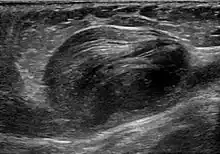

Abdominal aortic aneurysm involves a regional dilation of the aorta and is diagnosed using ultrasonography, computed tomography, or magnetic resonance imaging. A segment of the aorta that is found to be greater than 50% larger than that of a healthy individual of the same sex and age is considered aneurysmal.[10] Abdominal aneurysms are usually asymptomatic but in rare cases can cause lower back pain or lower limb ischemia.